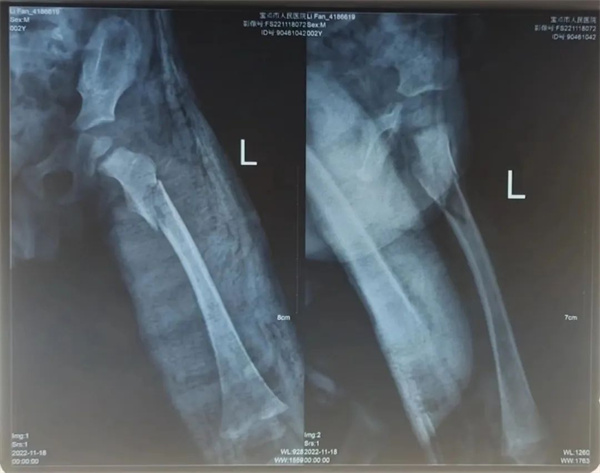

术后康复治疗期间,科室医护紧密关注患儿情况,从护理、搬动、大小便等方面全方位照顾,防止骨折移位。因为患儿年幼,护士长王艳和主管护士雷晓玲时常来观察、安抚。雷晓玲观察到患儿每次看到透视机器就会紧张、害怕,便为带来了自家孩子的玩具和零食来缓解患儿检查治疗过程中的恐惧心理。在科室医护的悉心治疗照料下,经过三周动态X线复查,患儿骨折端愈合良好,已经长出了骨痂,这就意味着孩子的骨头已经开始愈合了,家人也不用担心骨折处发生移位了。看着孩子一天天多起来的笑容,家属慢慢舒展开的眉头,这大概是科室医护历经三周的辛苦耕耘后最好的收获。

术后第三周基本完全恢复

12月3日,帆帆出院时,王文亮一再提醒家属要注意孩子的康复治疗,在骨折未完全愈合期间仍以制动为主,同时避免患肢负重。待患肢骨折愈合后,则要来院复查指导行功能锻炼。通常可通过肢体屈伸功能锻炼,可起到避免肌肉萎缩,防止关节粘连等,使受伤肢体的功能尽快恢复到小儿骨折前的正常状态。即将出院的小帆帆则拉着主管医生尚玉龙的手指头说:“我好了还要坐摇摇马呢!”